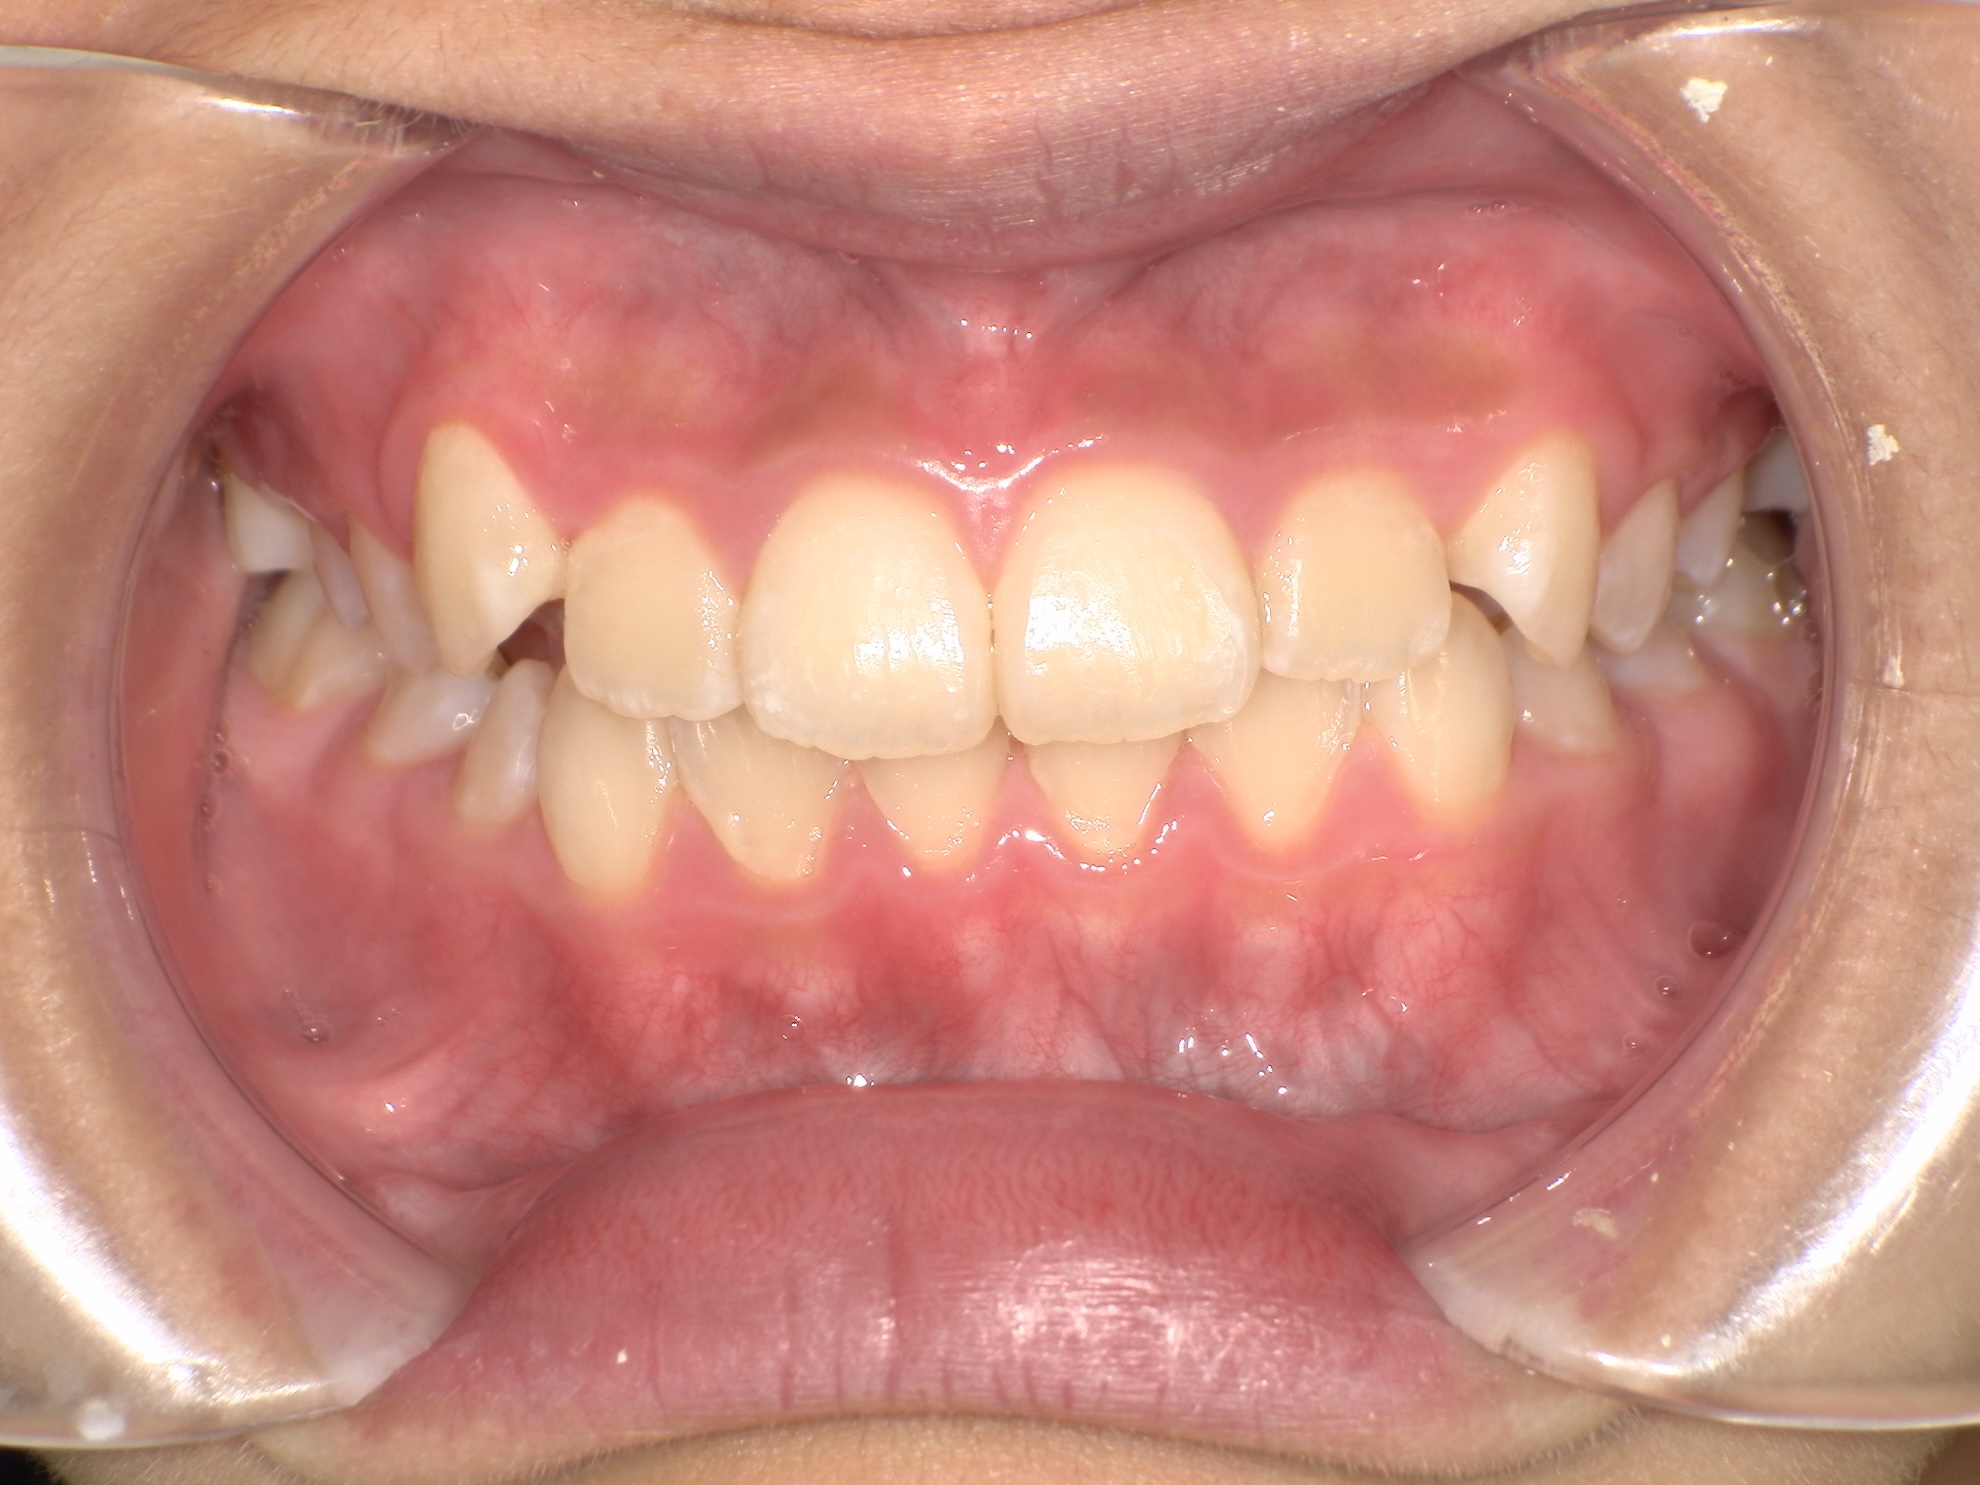

反対咬合(受け口)を改善しました

BEFORE

反対咬合の治療前

AFTER

反対咬合の治療後

年代・性別

8歳 男の子

主訴

上下反対の噛み合わせを治したい

診断

骨格性Ⅰ級、歯性Ⅲ級、機能性反対咬合

治療内容

アクティブプレート、部分的な唇側ワイヤー矯正、リテーナー

治療期間

3年

治療リスク

痛み、歯根吸収、歯肉退縮

治療費用

約40万円